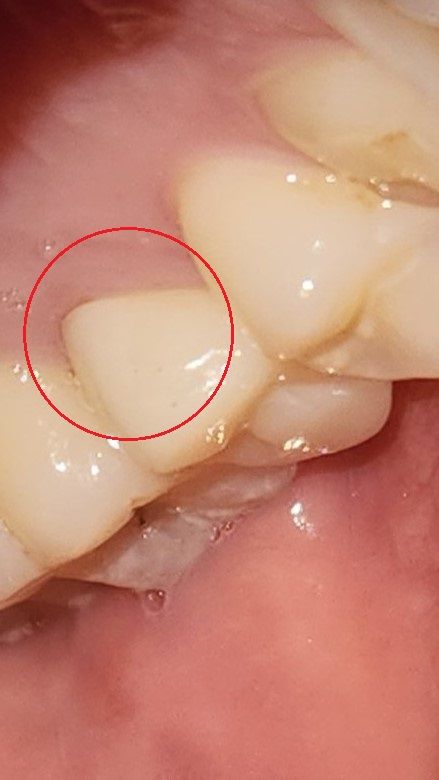

크라운이랑 잇몸사이에 틈새가 생긴거 같은데

치실을 쎄게 하다가 크라운이랑 잇몸사이에 틈새가 생긴거 같은데요

틈새 사이로 크라운 내부에 2차 충치가 생길 수 있는 문제가 있을까 걱정됩니다.

크라운과 치아 사이에 공간이 넓으면 2차 우식이 생길 수 있습니다. 사진상으로는 그다지 문제가 될 정도로 보이지 않으며 양치질 잘해주시면 됩니다.

보철물의 경계 부위는 약간 떠 있을 수 있습니다. 대부분 크게 문제를 발생시키지 않기 때문에 양치질을 할 때 잇몸을 살짝 눌러서 양치질을 해주는 것을 권유드립니다. 또한 워터픽을 사용한다면 잇몸 아래쪽도 세정을 할 수 있기 때문에 충치가 생기는 것을 방지하는 데 도움이 됩니다

보통 보철물 경계선을 잇몸보다 약간 아래에 설정하고 씌우게 되는데요

잇몸이 내려가게 되면 그 부분이 노출 될 수 있습니다.